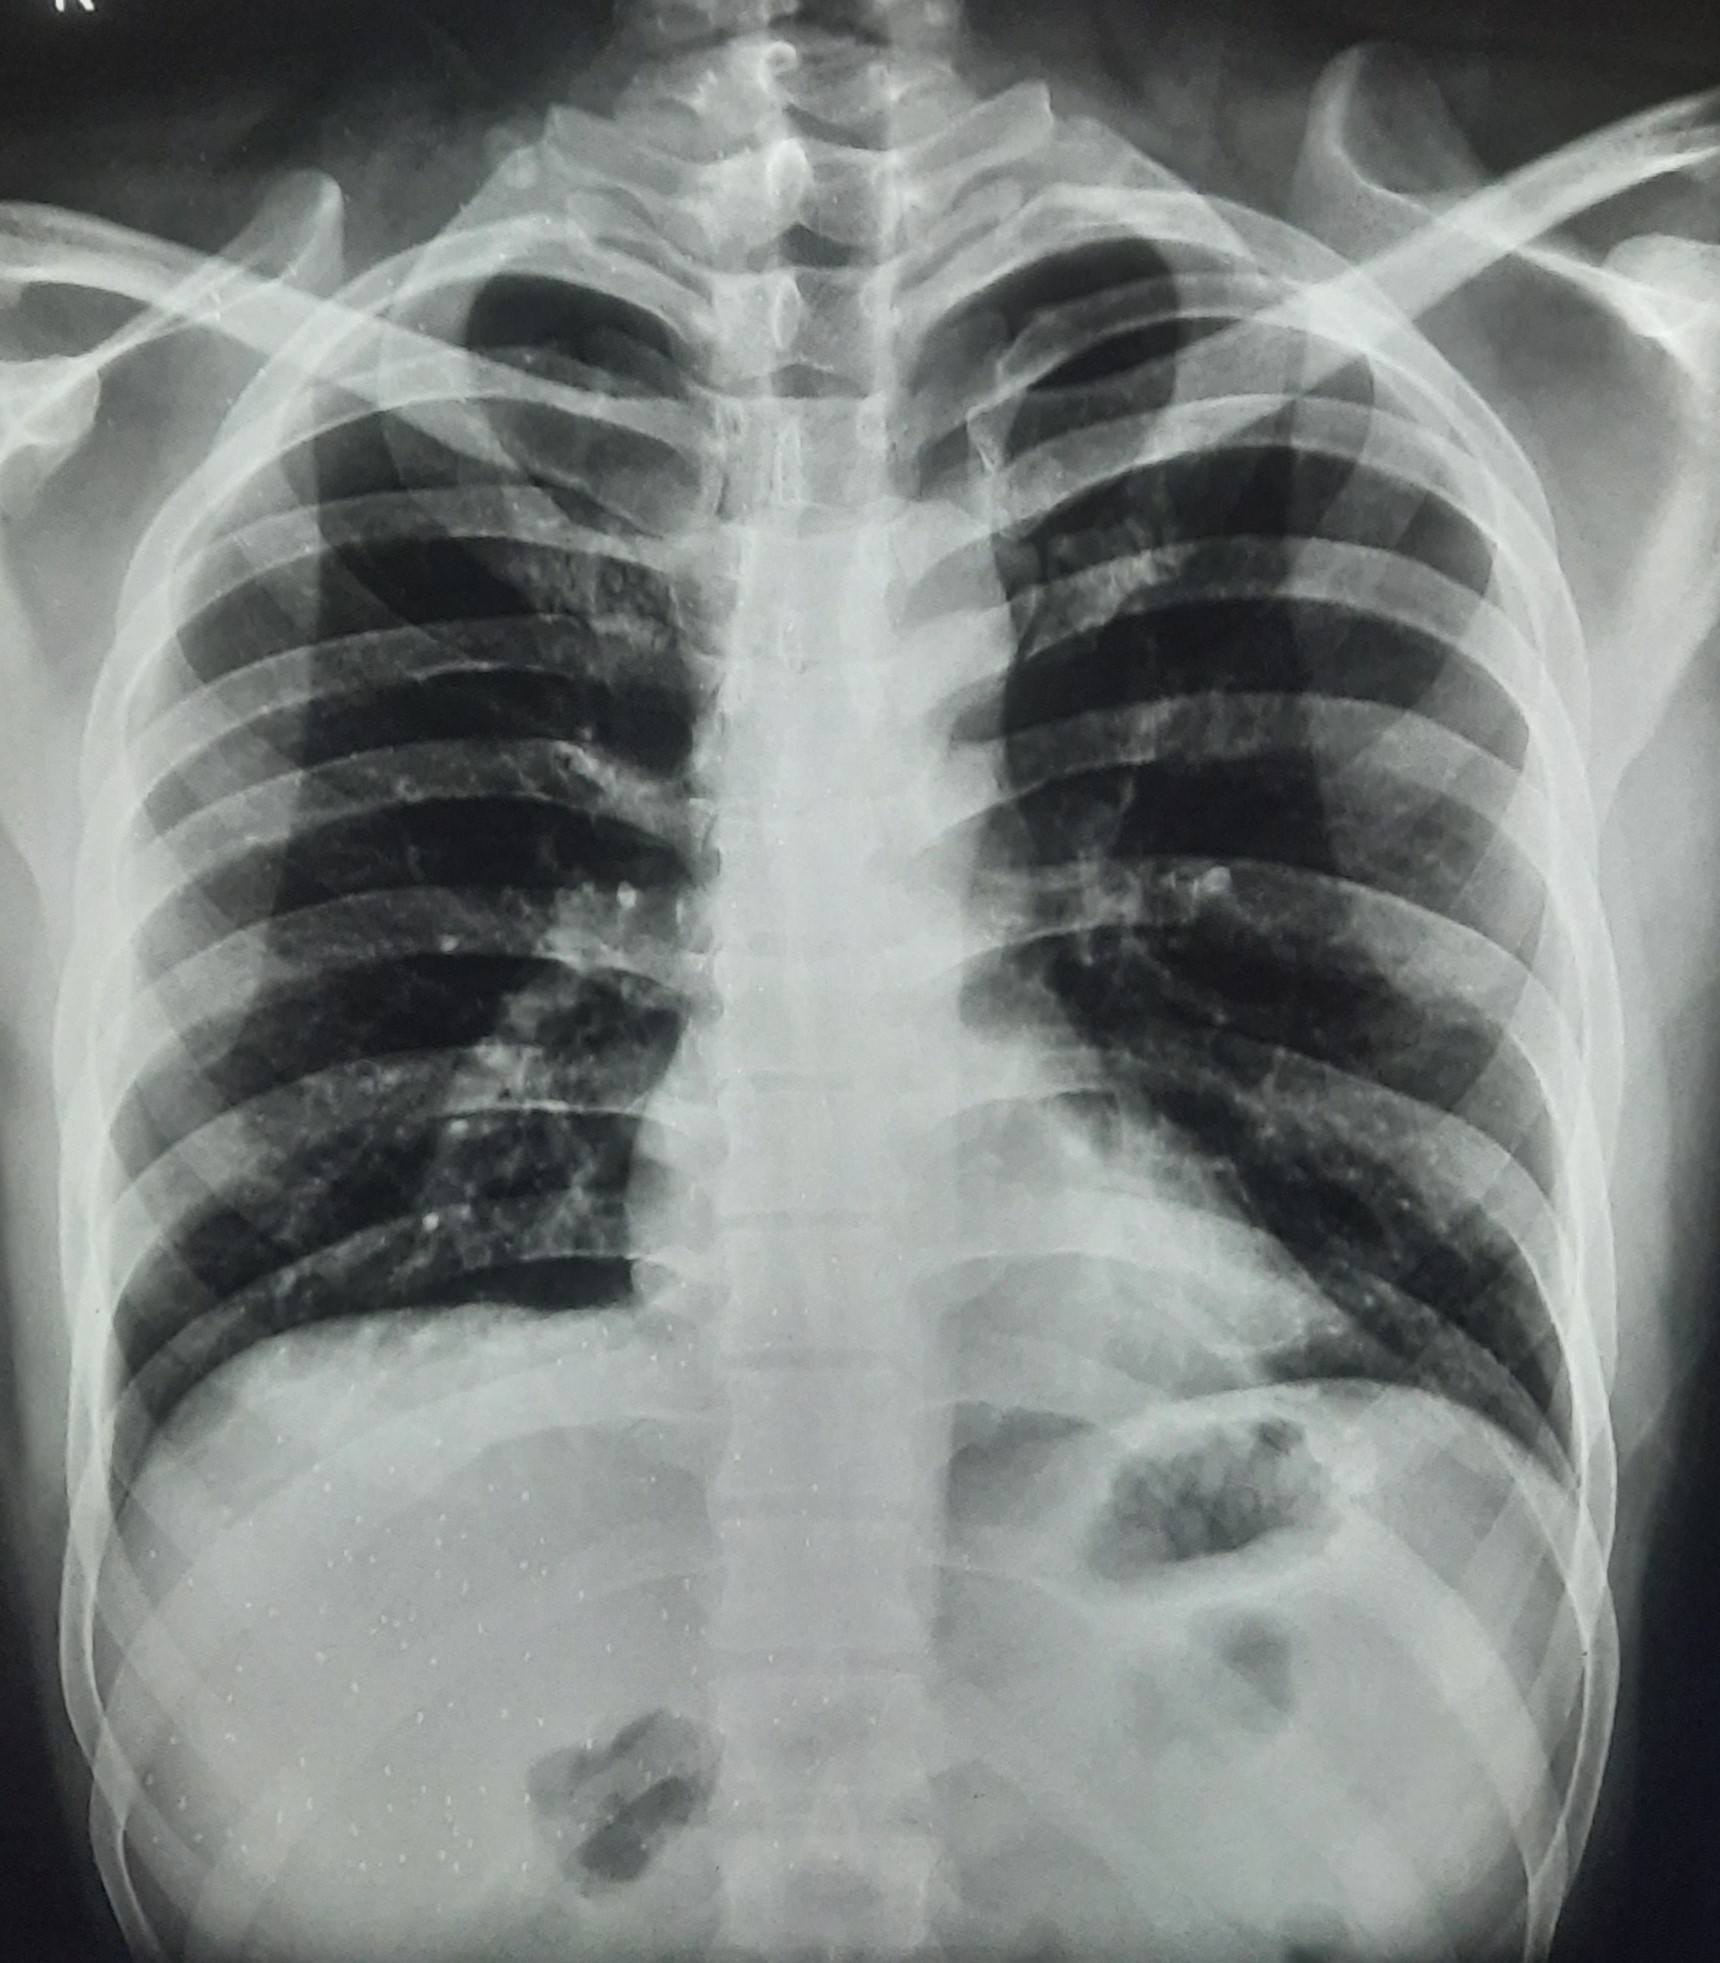

| 297 | IGGMC, Nagpur, Nagpur | P2 | 29-4175 | Sabina Parveen | Consent taken on Paper | 23 Yrs. |

Provisional Diag : PTB Reactivation

Final Diag : ? |

TB Case (Confirmed) | Bilateral Middle Lower Zone Pulmonary TB | Abnormality visible on x-ray |